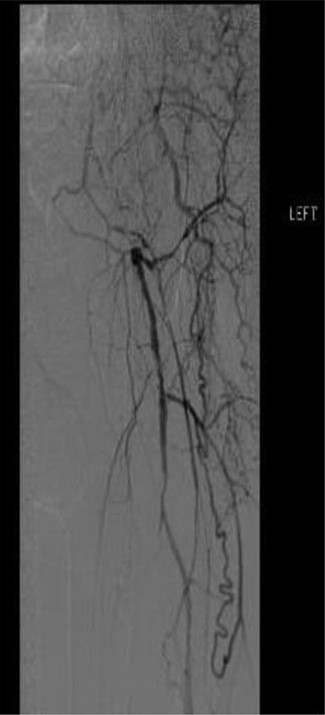

Workup began with noninvasive studies of the left lower extremity displaying aortoiliac occlusive disease and infrainguinal disease. Aortogram demonstrated a severely calcified aorta, patent left common iliac and proximal hypogastric arteries, with occlusion of the left external iliac, left common femoral and left superficial femoral arteries (Fig. 1). The right iliac system was patent apart from an occluded right hypogastric artery. A selective left lower extremity angiogram demonstrated reconstitution of the mid-to-distal profunda femoris artery (Fig. 2) to the proximal above-knee popliteal artery at the adductor hiatus (Fig. 3). Extensive collateralization was appreciated in the pelvis and lower extremity, between the residual left hypogastric artery and profunda femoris artery. Endovascular revascularization attempts were unsuccessful.

Selective left lower extremity angiogram demonstrating patent mid-to-distal profunda femoris artery and its collaterals

Selective left lower extremity angiogram demonstrating reconstitution of the above-knee popliteal artery at the adductor canal